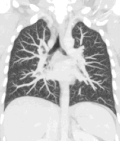

A CT scan can be used for detecting both acute and chronic changes in the lung parenchyma, the tissue of the lungs.[66] It is particularly relevant here because normal two-dimensional X-rays do not show such defects. A variety of techniques are used, depending on the suspected abnormality. For evaluation of chronic interstitial processes such as emphysema, and fibrosis,[67] thin sections with high spatial frequency reconstructions are used; often scans are performed both on inspiration and expiration. This special technique is called high resolution CT that produces a sampling of the lung, and not continuous images.[68]